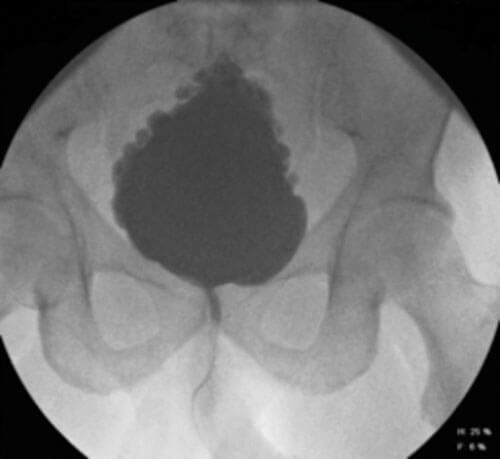

Figure 1: Fir tree bladder on VCMG (with reflux).

After reviewing an eight-year-old boy with nocturnal enuresis, urinary tract infections and a ‘Christmas tree’ bladder with upper tract compromise on imaging in the absence of any underlying neurological abnormality, he identified a new phenomenon and called it the non-neurogenic neurogenic bladder [2].

The precise pathophysiology of Hinman syndrome remains unclear. It is a type of functional bladder outlet obstruction, thought to be caused by voluntary contractions of the external urethral sphincter during voiding. It is understood to be an abnormal, learned response to uncontrolled bladder contractions which usually develops early in life [2]. Hinman and his colleague Baumann both proposed that this incoordination of detrusor-sphincter function can lead to both structural and functional changes including incomplete bladder emptying, recurrent urinary tract infections and a functionally small trabeculated bladder in the most severe cases with subsequent vesico-ureteric reflex resulting in hydronephrosis [7,8].

History and examination has to be thorough and specific to exclude underlying neurological abnormalities. Further evaluation should include completion of a bladder diary, uroflowmetry, ultrasonography of the urinary tract to check for any upper tract changes and to accurately measure post-void residual volume. Videourodynamic studies (VCMG) are used to help identify any bladder dysfunction, to assess the bladder outline, capacity, storage pressure, compliance and to look for vesico-ureteric reflux. Cystourethroscopy can also be performed to help exclude any anatomical obstruction. A dysfunctional voiding symptom score (DVSS) can be used to measure the severity of symptoms [14]. Magnetic resonance imaging of the lumbosacral spine should be reserved for those with neurological findings on examination or complex skeletal deformity on plain x-ray [15].